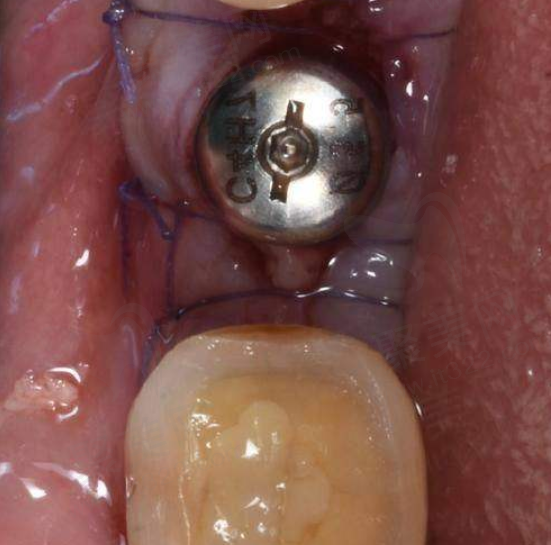

李静医生在种植牙领域有着出色的表现。她擅长口腔缺失牙种植治疗以及美学修复,尤其在一些复杂的种植修复方面有着丰富的经验和独特的技术。

对于前牙美学修复,李静医生能够精细把握牙齿的形态、颜色和排列,使修复后的牙齿与患者的面部整体美观相协调,达到自然逼真的成效。在处理多颗牙缺失、半口和全口缺失的复杂种植修复时,她熟练运用All on 4、无牙合种植后即刻修复技术、Tpp翼板种植技术等精良技术,为患者提供效率高、舒适的种植解决方案。这些技术能够大大缩短患者的治疗周期,减少痛苦,让患者更快地修复咀嚼功能。

此外,李静医生还擅长牙周炎的手术及非手术治疗。她深知牙周健康对于种植牙成功的重要性,在种植前会对患者的牙周状况进行全方面评估和治疗,确保种植手术的成功几率和长期稳定性。她凭借不错的医术和丰富的经验,为众多患者解决了牙齿缺失的难题,赢得了患者们的高度认可和好评。